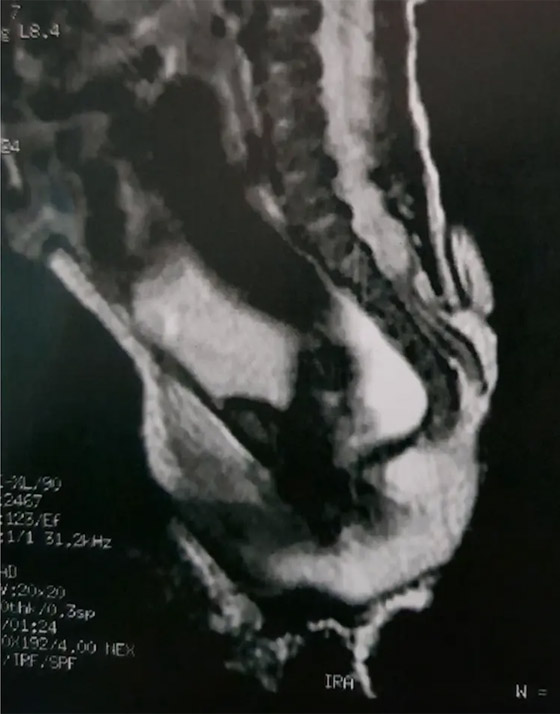

في التفاصيل، ولدت الفتاة التي لم تذكر تقارير الجراحين هويتها، مصابة بـ"السنسنة المشقوقة"، وهي عيب خلقي نادر في العمود الفقري يحدث في الرحم، ويسبب فجوة في العمود الفقري. وهذه الحالة هي نوع من عيوب الأنبوب العصبي، وهو بنية بالجنين النامي تصبح في النهاية دماغ الطفل والحبل النخاعي والأنسجة التي تحيط بهما.

فيما تمكن الجراحون من إزالة الذيل. وكشف الأطباء من مستشفى GRENDAAC للأطفال في ساو باولو، أن الذيل انتشر من المنطقة القطنية العجزية، وهي المنطقة التي تربط العمود الفقري بالحوض. كما شخص الفريق هذه الأنسجة الزائدة على أنها "ذيل بشري زائف". يشار إلى أنه تم تسجيل أقل من 200 حالة من هذه الظاهرة، وهي حالة غير طبيعية أثناء الحمل.